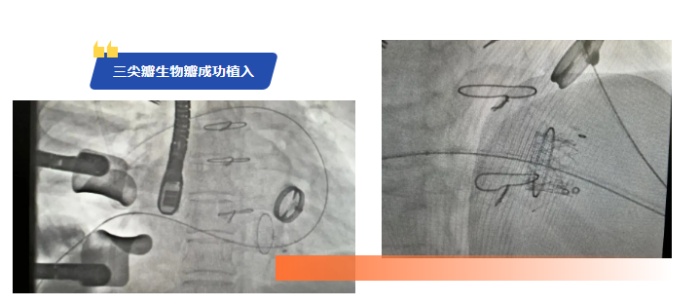

在手術(shù)準(zhǔn)備階段,心胸外二科與心血管內(nèi)科的專家們共同為陳女士制定了詳細(xì)的手術(shù)方案,對每一個環(huán)節(jié)都進(jìn)行了精心的設(shè)計和預(yù)演。在手術(shù)過程中,心胸外二科與心血管內(nèi)科專家憑借精湛的外科技術(shù)和導(dǎo)管操作技術(shù),精準(zhǔn)地將人工瓣膜送達(dá)病變部位。

整個手術(shù)過程如同一場精密的戰(zhàn)役,每一個步驟都需要精準(zhǔn)無誤。經(jīng)過1個小時的緊張奮戰(zhàn),手術(shù)終于順利完成。術(shù)后,陳女士在心胸外二科醫(yī)護人員的精心護理下,恢復(fù)狀況良好,全身水腫的癥狀得到了明顯改善。